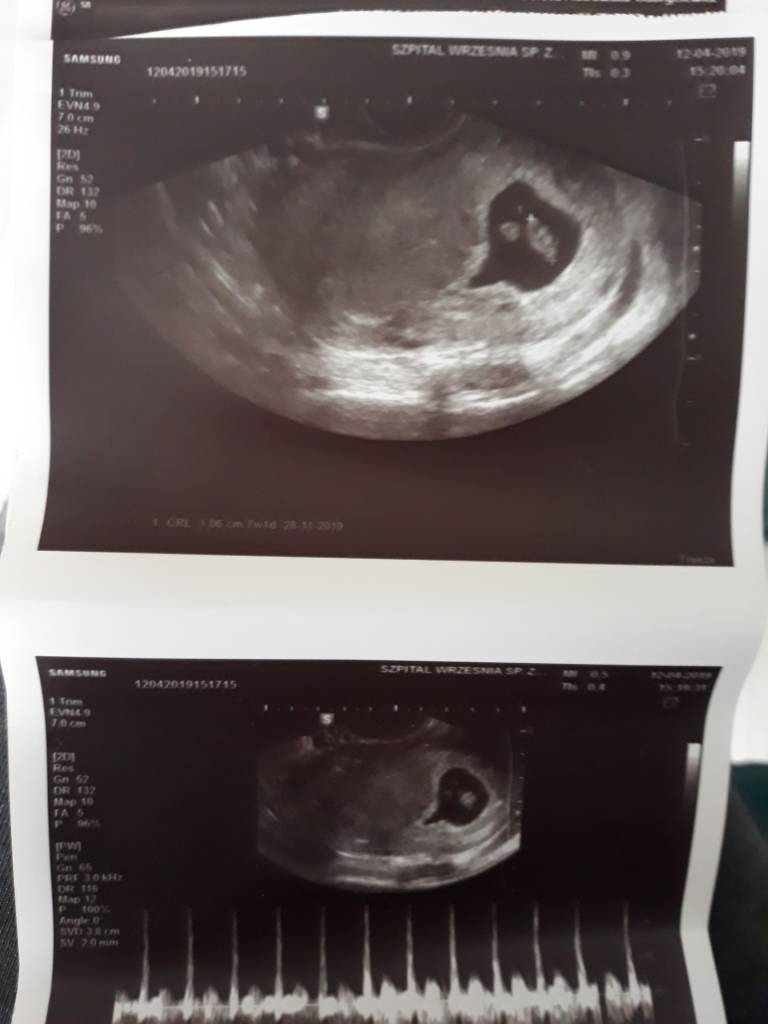

Okazało się wczoraj, że dzidziok miał 190/min i mój lekarz powiedział że to bardzo dobrzeDaj koniecznie znać!

Dzięki. Super, że z malcem wszystko ok! :-)Okazało się wczoraj, że dzidziok miał 190/min i mój lekarz powiedział że to bardzo dobrzekoło 12 tyg ma się unormować

U nas 146 i nic nie było mowy że niskie.U mnie wczoraj 1,09cmtylko lekarz powiedział, że tętno mogłoby być wyższe, a było 136, to 7tc i 1 dzień